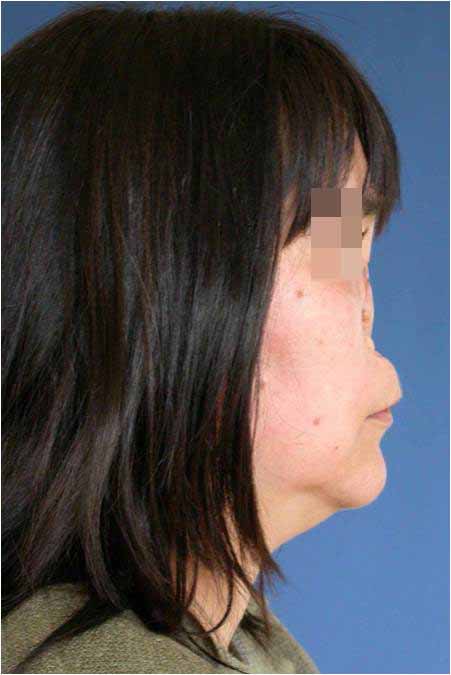

Тежките вродени или придобити лицеви деформации изискват първоначална реконструкция на скелетната основа на лицето. Тя ще подобри позицията и на меките му тъкани. В последствие за детайлизиране на резултата могат да се приложат и други естетични корекции.

Лицева корекция преди и след лечението – случай на доц. Джоров

Корекция на брадата преди и след лечението – случай на доц. Джоров